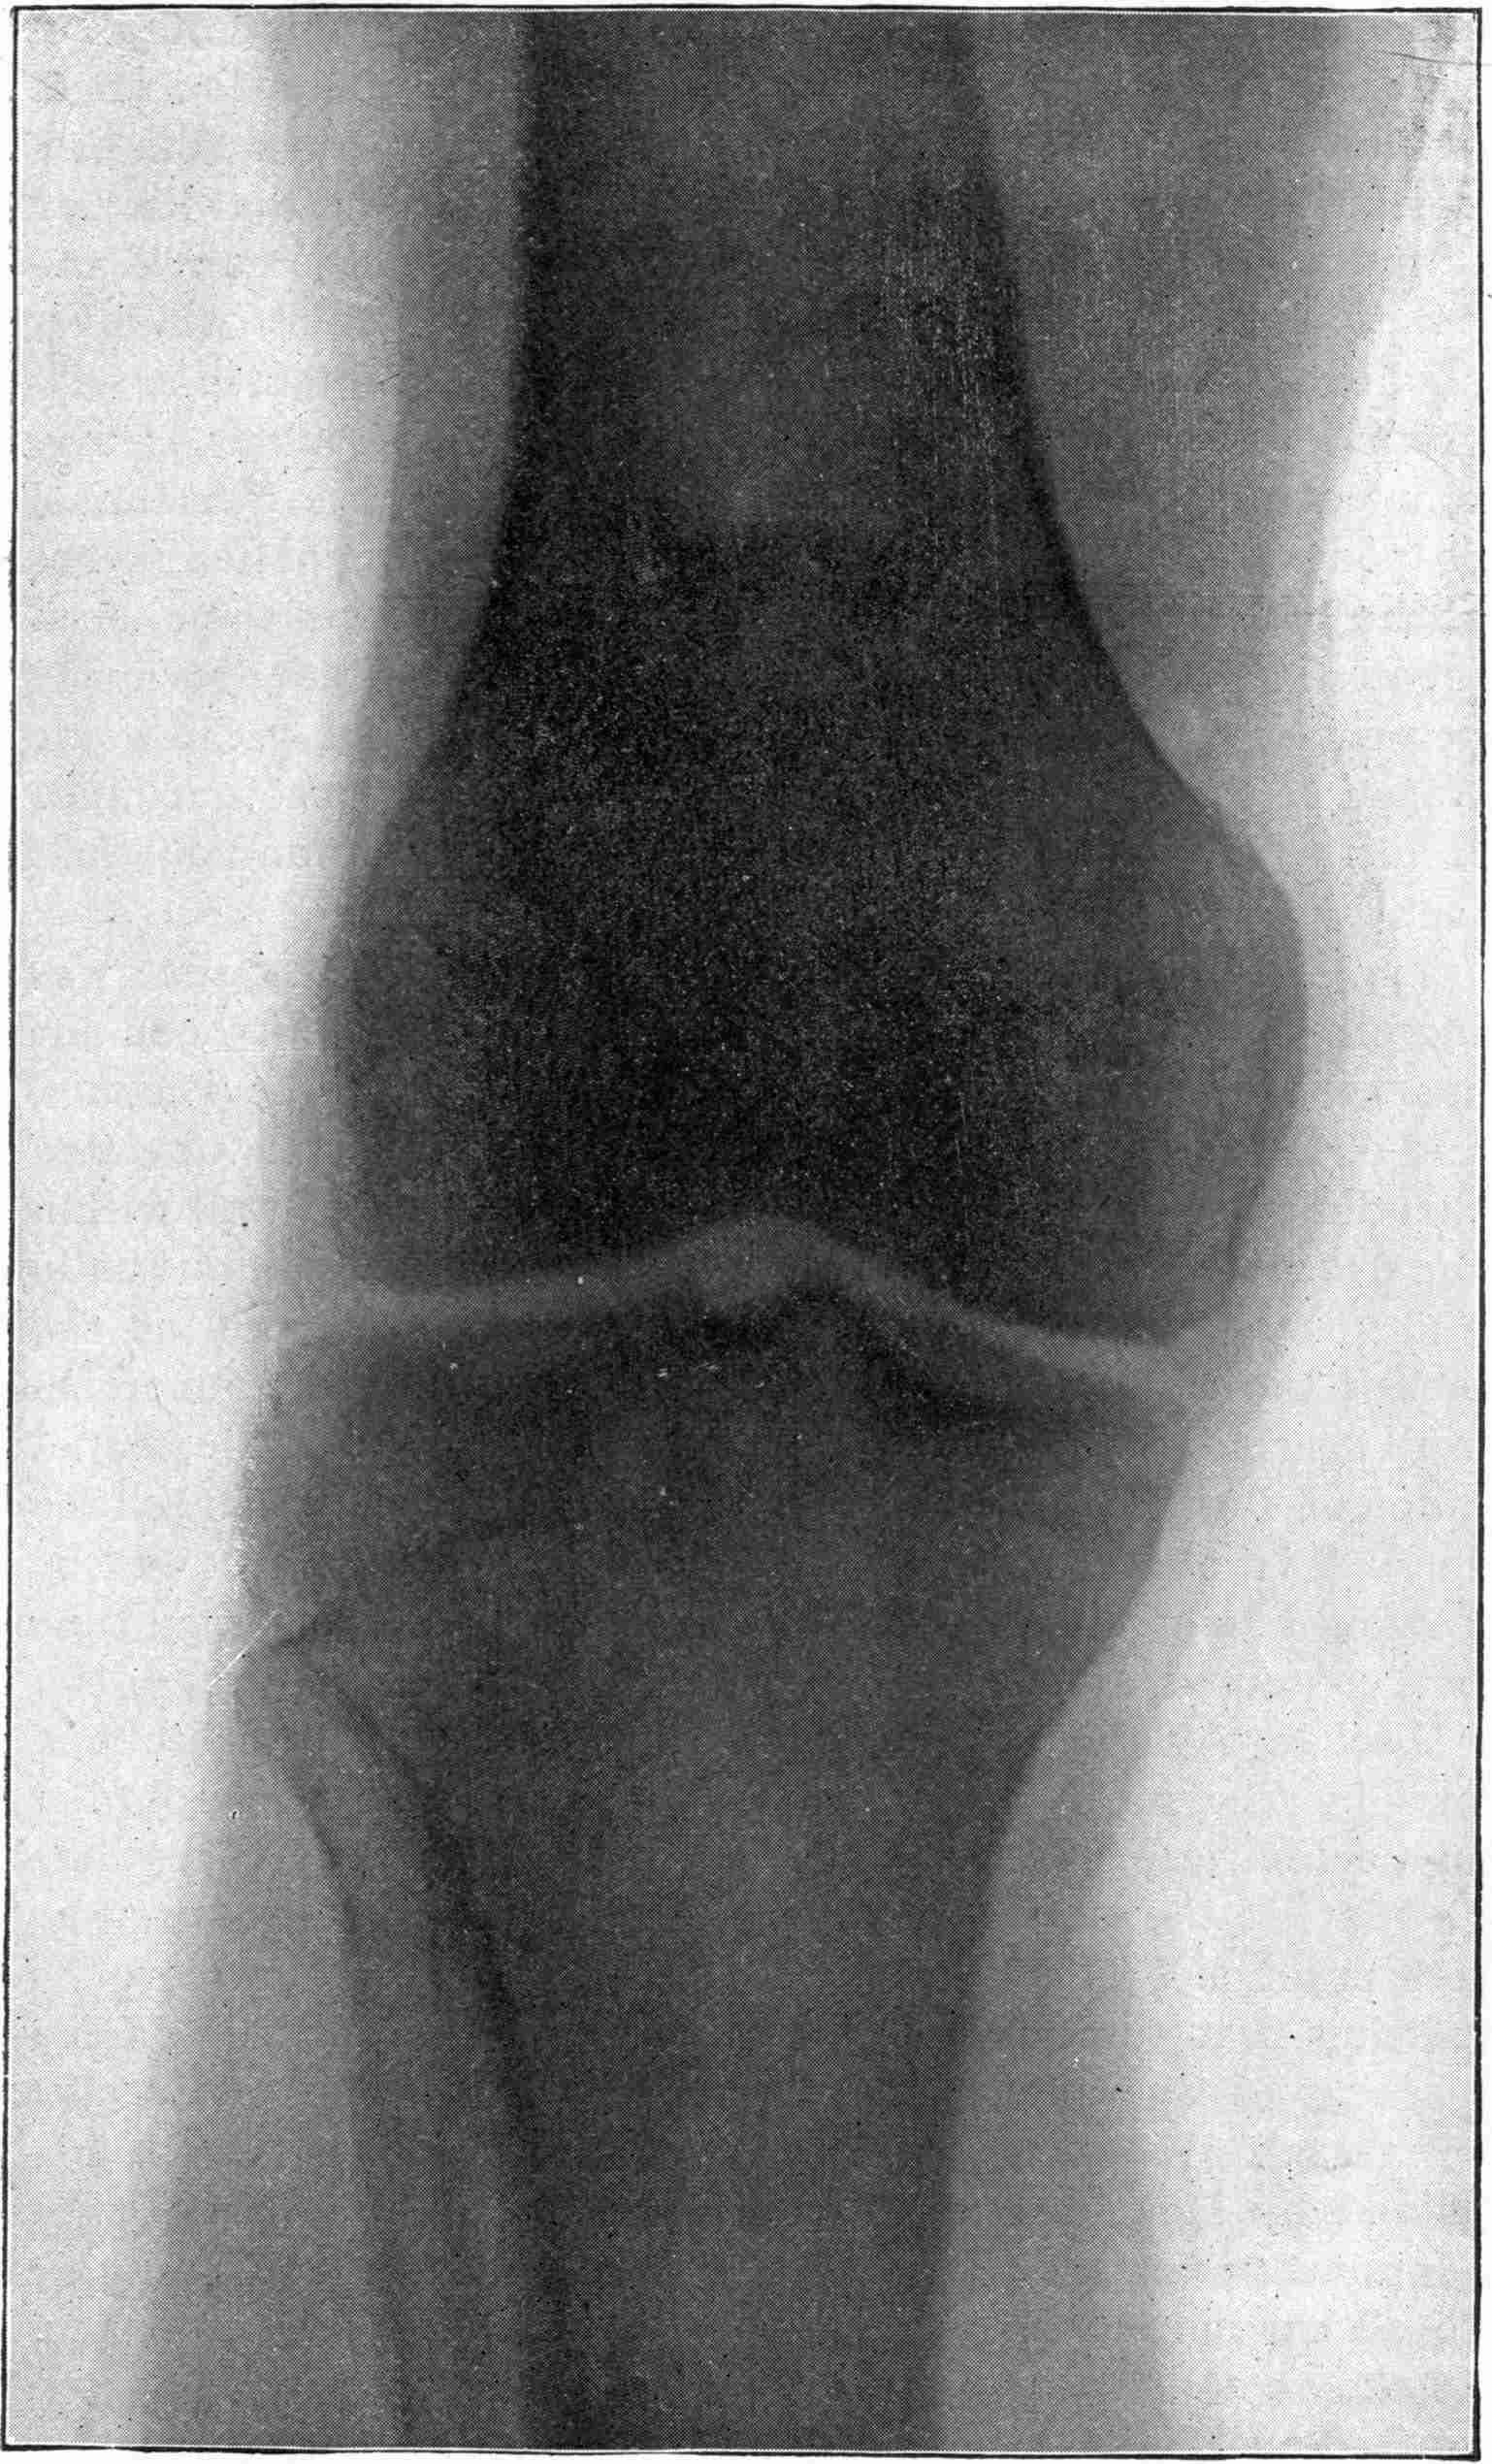

Fig. 4.—Knee, Knickerbocker Buttons, Bullet in Femur.

FROM SCIAGRAPHS BY PROF. DAYTON C. MILLER. § 204.

117. Transposition of Phosphorescent Spot and of Cathode Rays without a Magnet. Salvioni, Elster, Geitel, and Tesla